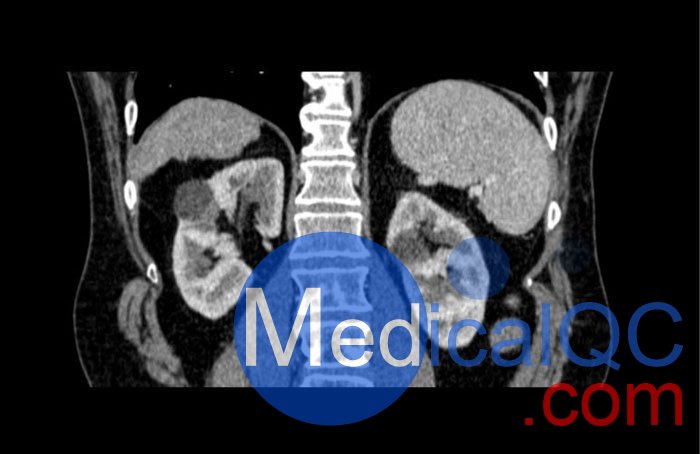

WEK53-04肝硬化腹部模體,WEK53-04腹部模體代表膽囊切除術(shù)后的腹部,帶有小夾子。肝臟有肝硬化的典型體征,在第三腰椎水平植入下腔靜脈過濾器。兩個腎臟都有囊性病變,左側(cè)有一小塊腎結(jié)石。

真實模擬脈管系統(tǒng)、骨骼和軟組織,包括肝臟、胰腺、脾臟、腎上腺、腎臟、胃、小腸和結(jié)腸。

• 肝硬化

• 膽囊切除術(shù)

• 下腔靜脈濾器

• 腎囊腫

• 腎結(jié)石

• 淋巴結(jié)腫大

SAG: